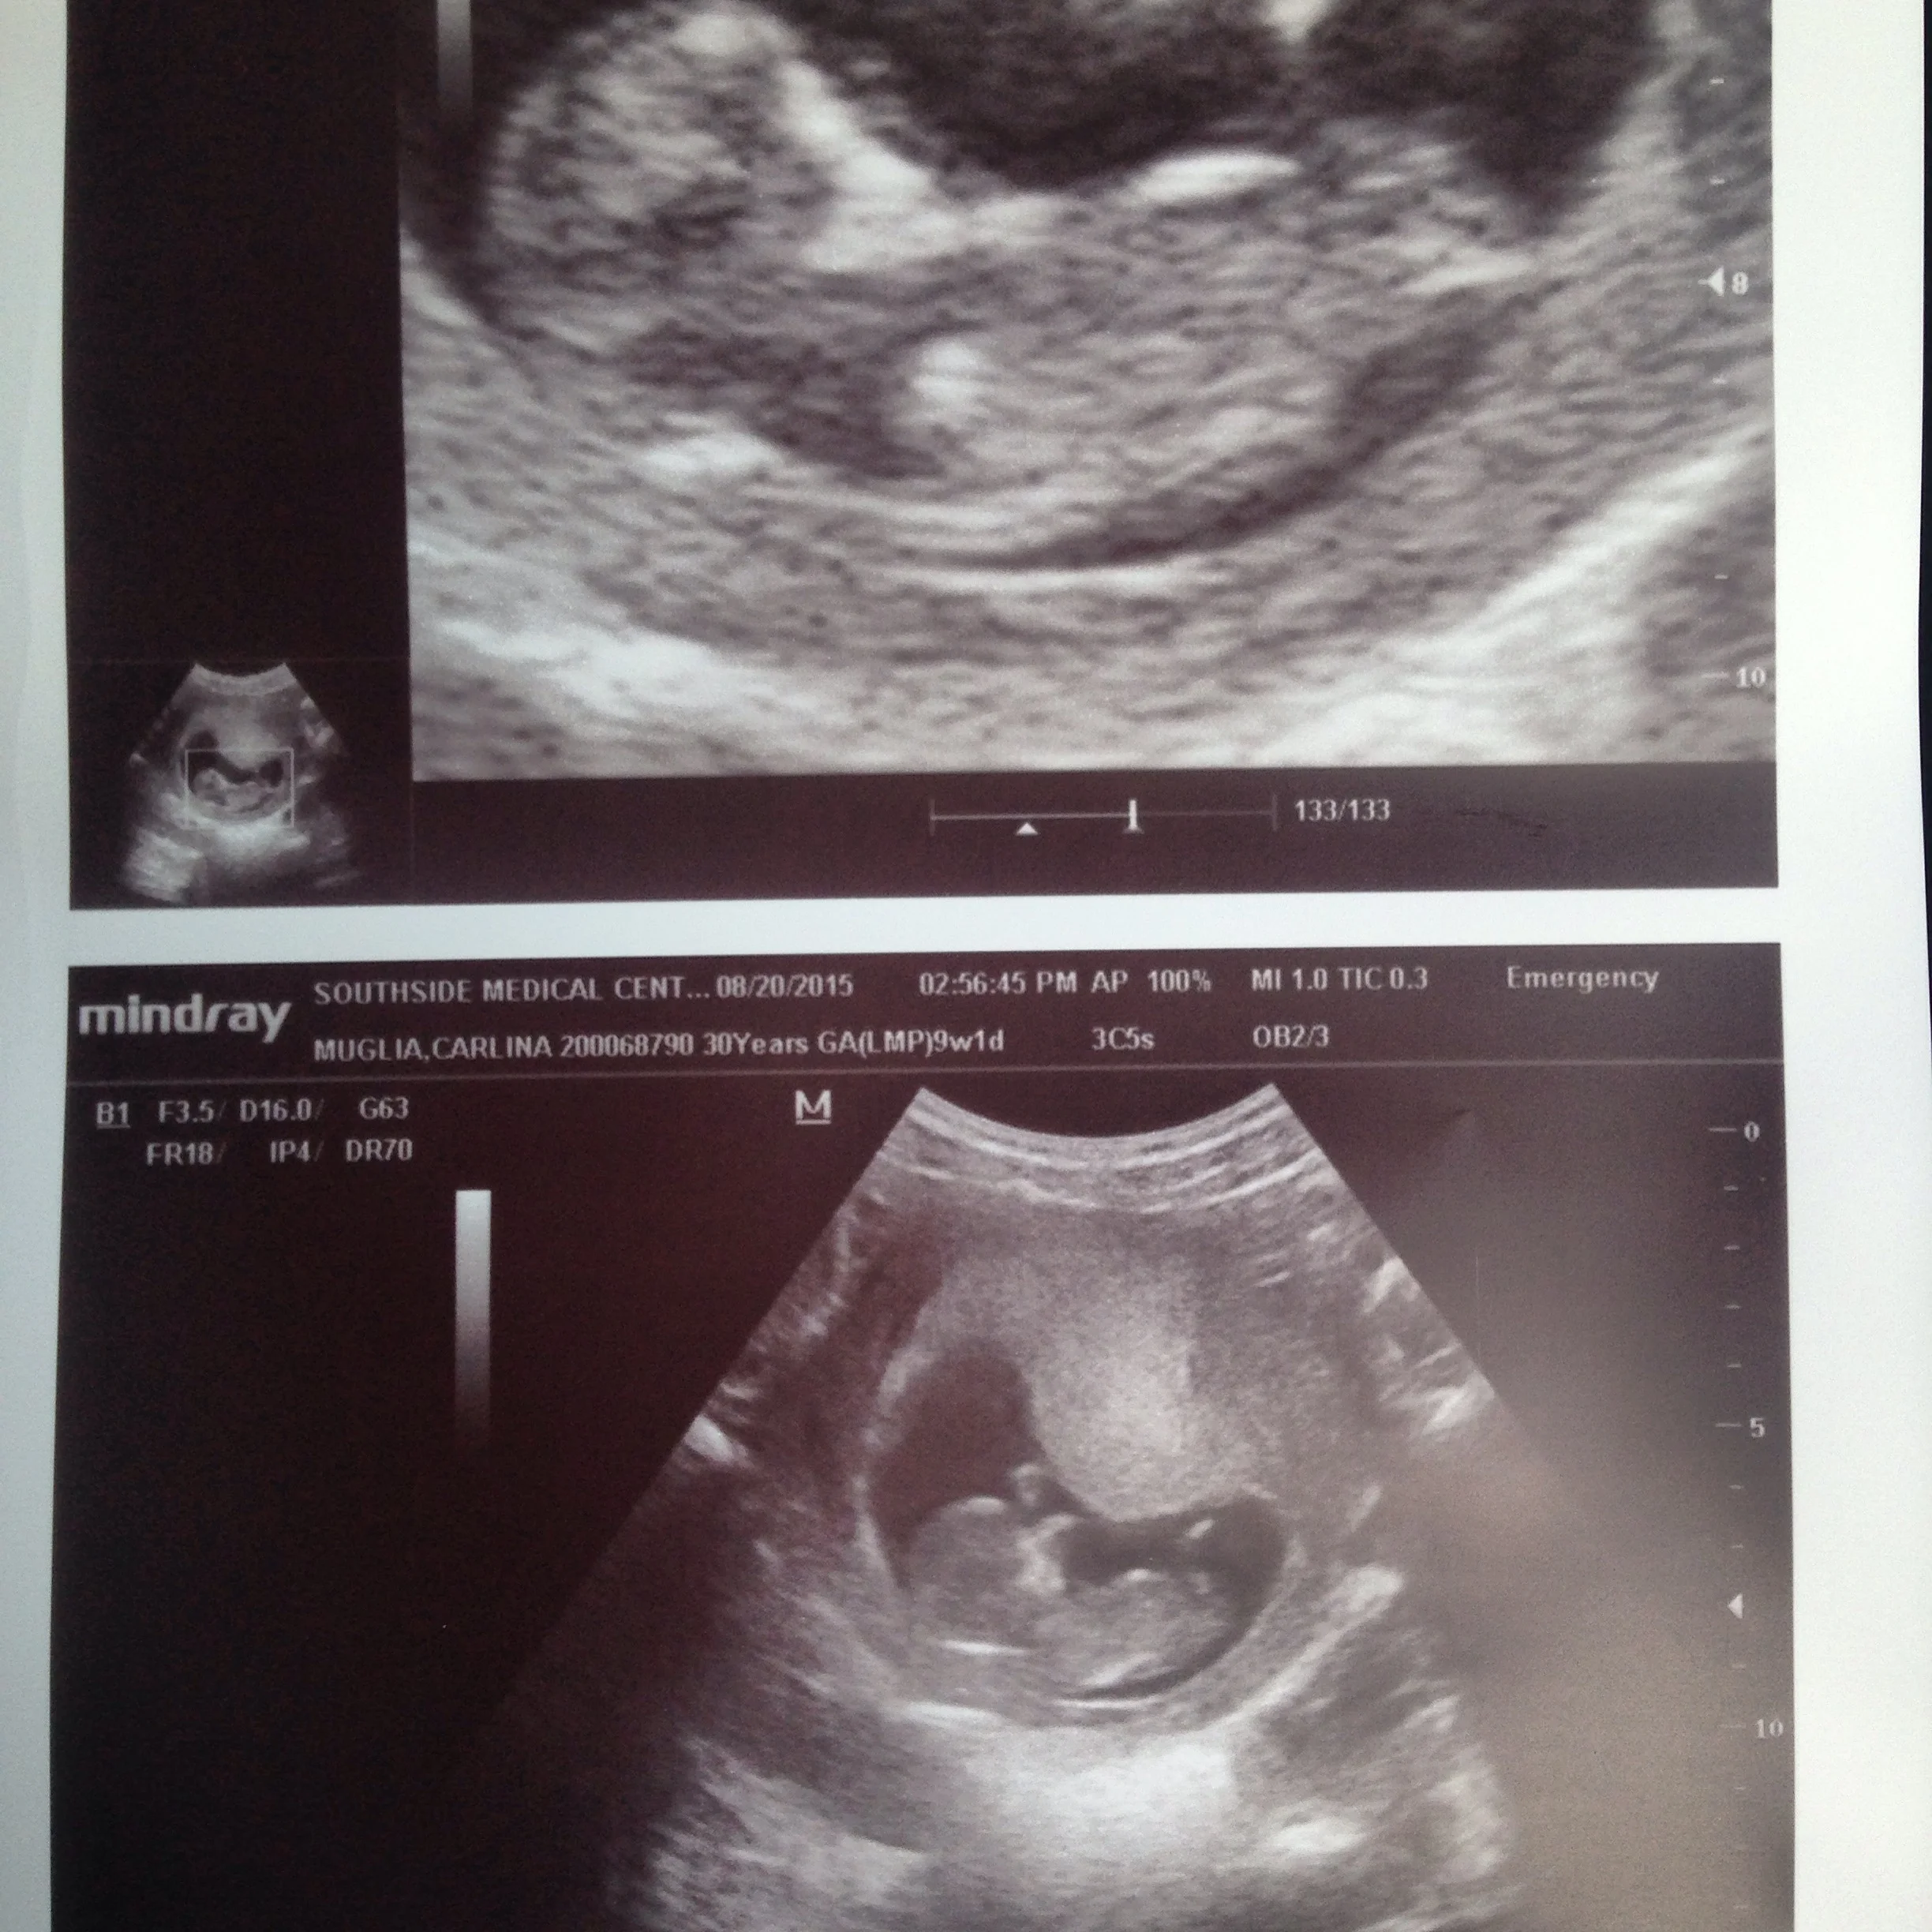

August 20, 2015: 9wks1day - Baby has a heartbeat and the urge to dance apparently.

I was under the impression that it takes a couple of months to get pregnant after a miscarriage. I think that gestalt was based on the assumption that the woman is going to have some level of PTSD and still be emotionally distraught and is actually not based on biology...cuz here I am 9wks and 3 days into my first pregnancy round 2.

Thank you for the extreme outpouring of support in the last couple of days. We are so happy to share this with our friends and family and so full of gratitude for this chance to pick up anew and love this baby. Several of you have asked for pictures of my "bump." Y'all, this is my first pregnancy and I have strong yogi-abs. So below are the pics...very underwhelming. If it wasn't for the ultrasound I would still be skeptical...